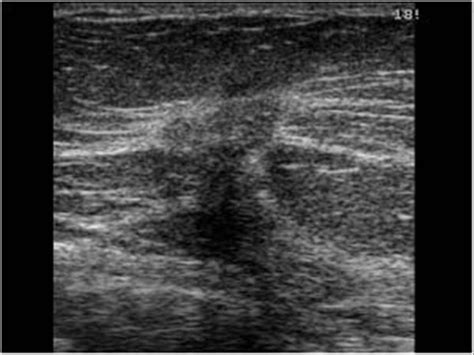

Invasive ductal carcinoma (IDC) is the most common type of breast cancer. It starts in the milk ducts and then invades the surrounding breast tissue. Invasive means the cancer cells have spread beyond the ducts into nearby tissues. Metastatic , on the other hand, means the cancer has spread from the breast to other parts of the body, such as the bones, lungs, liver, or brain. This spread occurs when cancer cells break away from the original tumor and travel through the bloodstream or lymphatic system to other areas.

Early detection through regular screening, such as mammograms, and prompt diagnosis are vital in preventing the progression of invasive ductal carcinoma to the metastatic stage. When breast cancer is detected early, treatment is often more effective, and the chances of a full recovery are higher. So, regular check-ups and awareness of breast health are key.